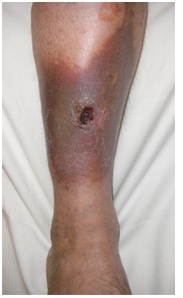

The longer the clot stays in venous channels it damages the valves inside veins leading to both structural and functional failure of venous blood return. This particular scenario can leave a patient with a permanent irreversible swollen limb with hardened discolored skin and Ulcers, in particular around ankle and lower legs.

This condition is called post DVT syndrome (Post thrombosis Syndrome PTS). PTS can be crippling and functionally impair many people and unfortunately with discolored and ulcerated legs will be a social problem to many people. Consulting a Vein Specialist in Naples early on can help prevent these complications and provide guidance on treatment options before symptoms progress.